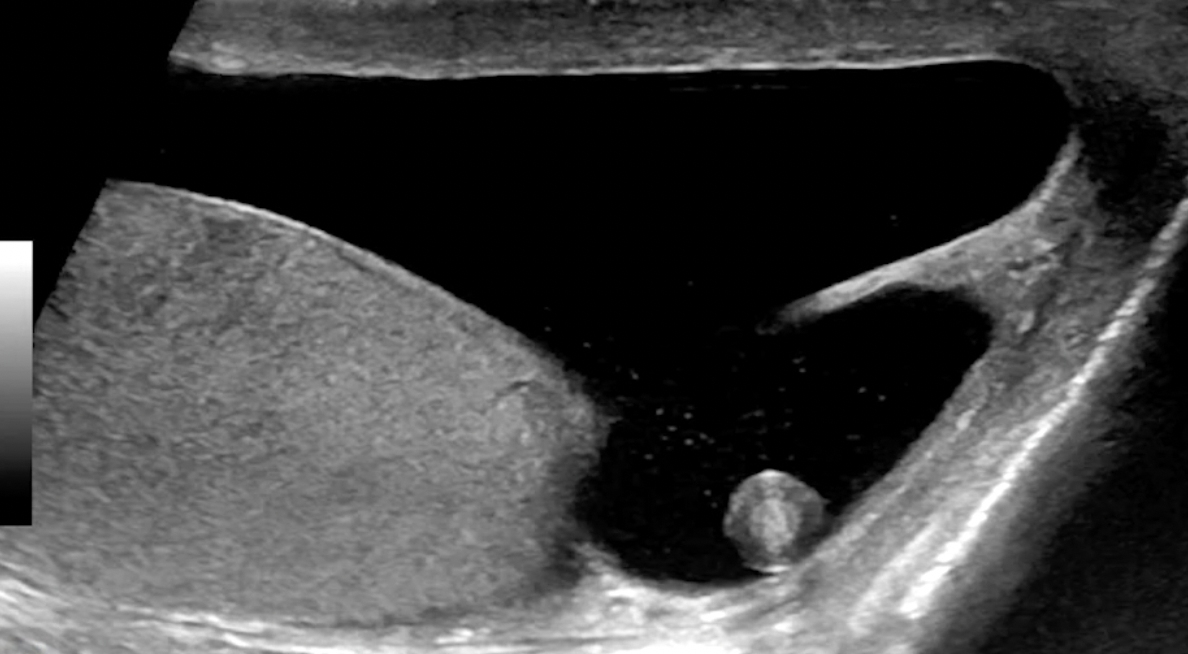

Scrotal Pearl

• Testicular appendage essentially twists off and just sits within the scrotum and the calcifies

Epididymal Cyst & Spermatocele

• Both look like a simple cyst next to testicle

• Anechoic with thin wall

• Only can tell difference if you aspirate them and spermatocele will have sperm, the epididymal cyst will have simple fluid